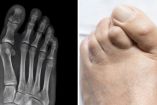

¿Conoces a alguien que sufra de juanetes?, ¿a qué se debe esta deformación?

Una de las principales molestias que puede haber en los pies, puede ser causada por los juanetes. Es un problema que afecta tanto a mujeres como a hombres. Además de ser dolorosos, modifican la estética. ¿Por qué salen?